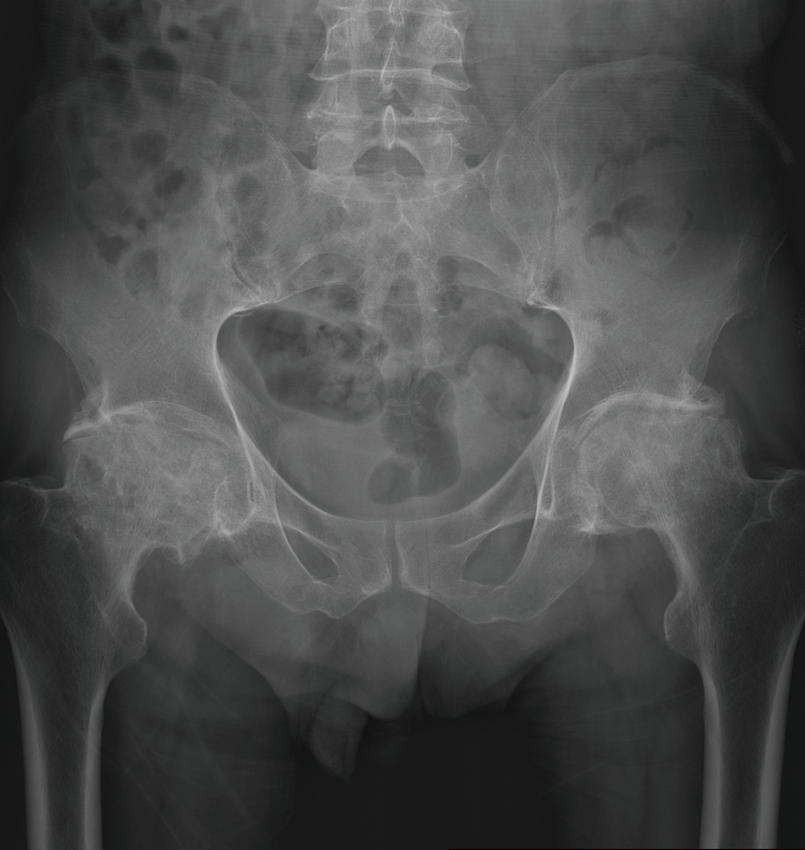

病例1 :使用骨科机器人辅助系统对股骨头坏死患者进行全髋关节置换手术,术后假体安放位置满意,角度精准